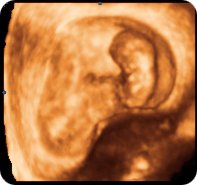

Ултразвучниот преглед во оваа фаза од бременоста е карактеристичeн поради тоа што ембрионот, иако е многумал, веќе наликува на бебе, а може да се забележи и негово движење. Особена радост за идните родители е прикажувањето на нивното бебе по прв пат, неговите движења и приказот на неговото срце кое се гледа на мониторот. Прегледот опфаќа и испитување со доплер, при што идните родители може да го слушнат срцето на бебето. Сите овие моменти се значајни за идната мајка и нејзиниот партнер. Присуството на обајцата родители помага во формирањето на една посилна емотивна врска помеѓу партнерите која делува позитивно на мајката, на текот на бременоста, на породувањето и понатаму при воспитувањето на детето кое сега е големо само неколку сантиметри.

Поточно, на овој преглед повторно се мери должината на ембрионот (CRL) која изнесува околу 25 mm.